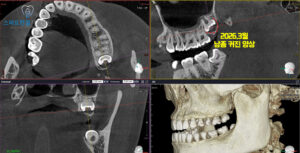

2026.3월

<위쪽 사랑니 낭종 크기 커진 양상>

이후 일 년 뒤 정기검진 위해 재내원하셨는데요.

파노라마를 촬영하여 확인해 보니,

왼쪽 위 사랑니 주변의 낭종이

일 년 전 보다 더 커진 것을 확인할 수 있었어요.

정밀한 확인을 위해 CT도 촬영하여

비교해 보기로 했어요.

CT를 촬영하여 확인해 보니,

일 년전과 비교하여

낭종이 확실히 커진 모습을 볼 수 있었어요.